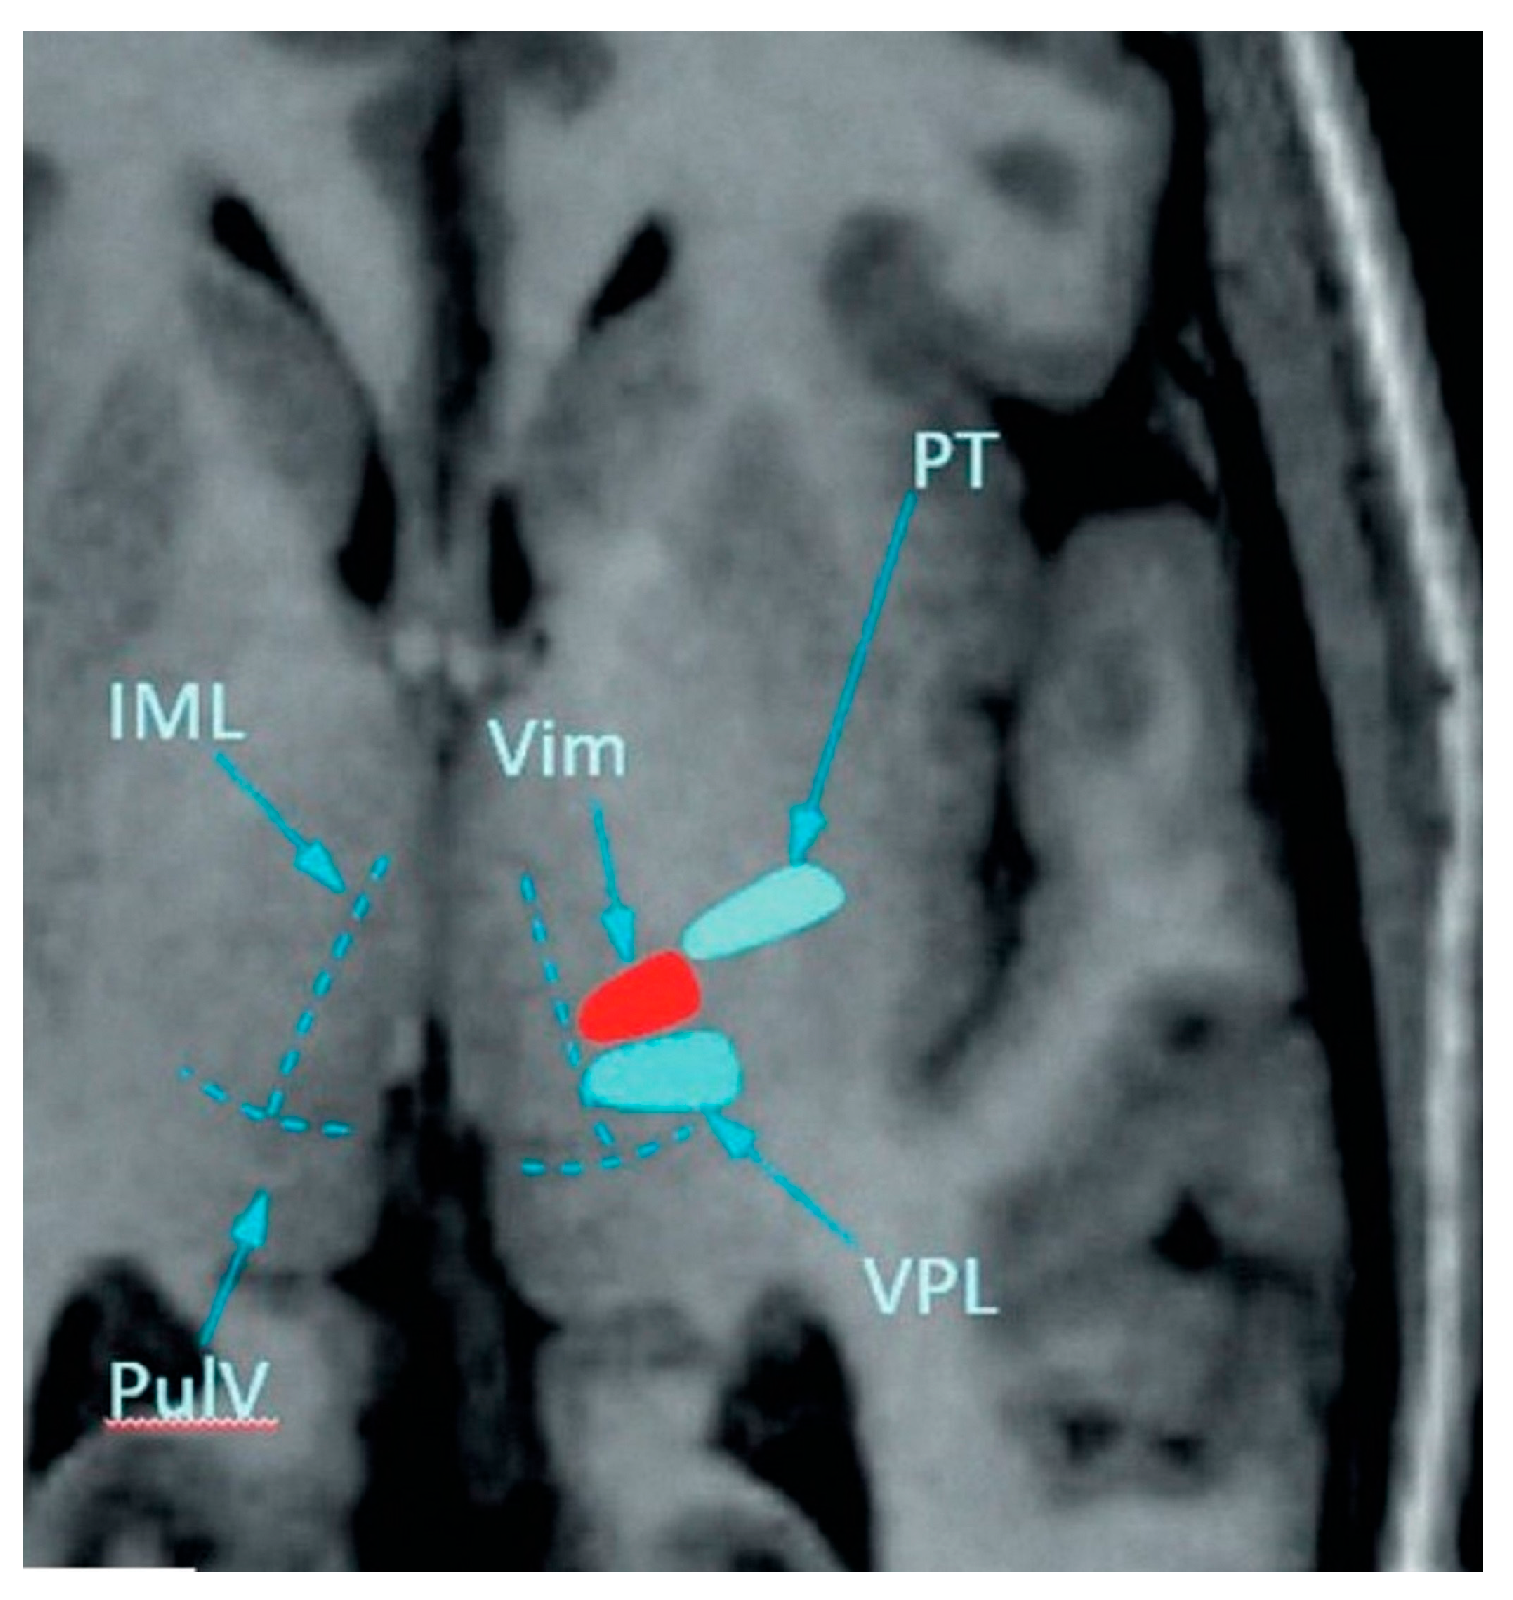

3.2.5. MRI Changes

| Before MRgFUS | 3 hrs Post-MRgFUS | Day 2 Post-MRgFUS | 3 Months Post-MRgFUS | 6 Months Post-MRgFUS | 12 Months Post-MRgFUS |

|---|---|---|---|---|---|

| NUCLEUS | |||||

| - | 194 [157; 238] | 394 [314; 504.5] | 29 [12; 52] | 9 [2; 20] | 9.5 [4; 24.75] |

| EDEMA | |||||

| - | 841 [709–1101] | 2718.5 [1974.5; 3426.25] | 37 [13.5–50.0] | 18 [0.5; 44] | 8 [0; 16] |

| FRACTIONAL ANISOTROPY | |||||

| 0.39 [0.36; 0.45] | 0.15 [0.13; 0.17] z = −4.014; p = 0.0001 * | 0.16 [0.14; 0.19] z = −3.823; p = 0.0001 * | 0.31 [0.25; 0.34] z = −2.897; p = 0.0038 * | 0.32 [0.26; 0.36] z = −1.334; p = 0.182 * | 0.32 [0.27; 0.57] z = −0.405; p = 0.687 * |